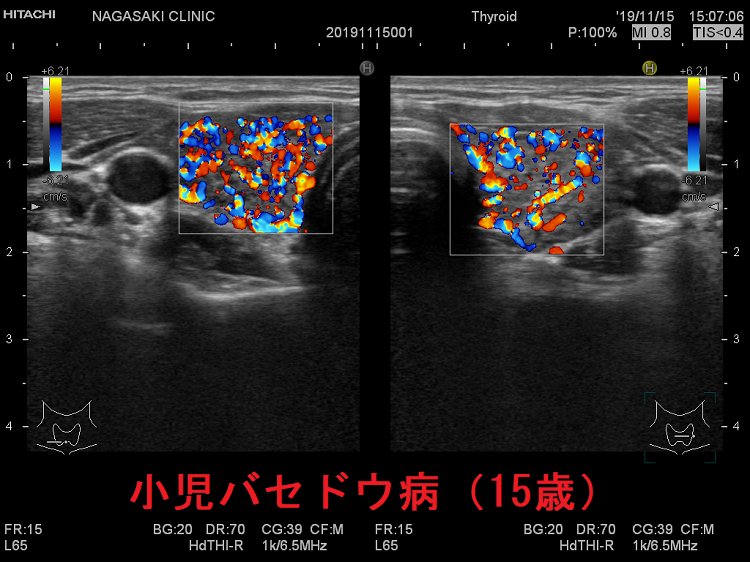

小児バセドウ病(15歳)超音波(エコー)所見は、基本的に成人と同じです。年齢ごとの正常甲状腺サイズの統一基準が無いため、比較は難です。